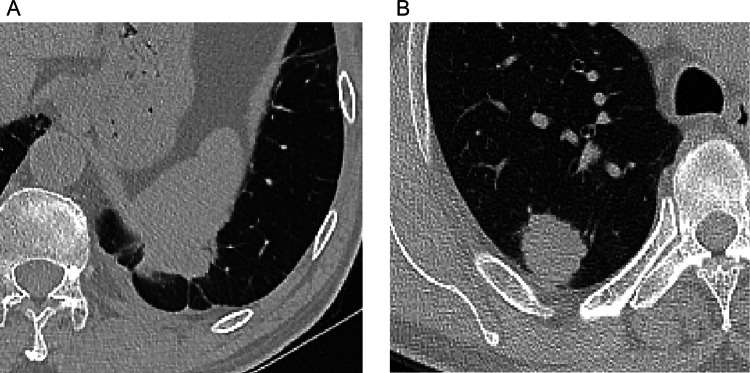

Univariate analysis showed that tumors with smaller DLP (p < 0.001), larger pleural contact length (p < 0.001) and pleural contact angle (OR = 4.57, 95% CI 1.92, 10.84 for score 1; OR = 3.28, 95% CI 1.56, 6.87 for score 2; p < 0.001), and pleural attachment (OR = 4.57, 95% CI 1.92, 10.84; p < 0.001) were more likely to develop VPI (Table 3; Fig. 2). Additionally, the CT semantic features of the primary tumor did not show statistical significance (Table S4).

Fig. 2.

A In a case of lung adenocarcinoma with VPI, the CT scan lung window image reveals the tumor's positioning beneath the pleura, with pleural attachment and a long pleural contact length characterized by an obtuse angle of contact. B Conversely, in a case of lung adenocarcinoma without VPI, the CT scan lung window image depicts the tumor located beneath the pleura, with a shorter curve length and an acute angle of contact